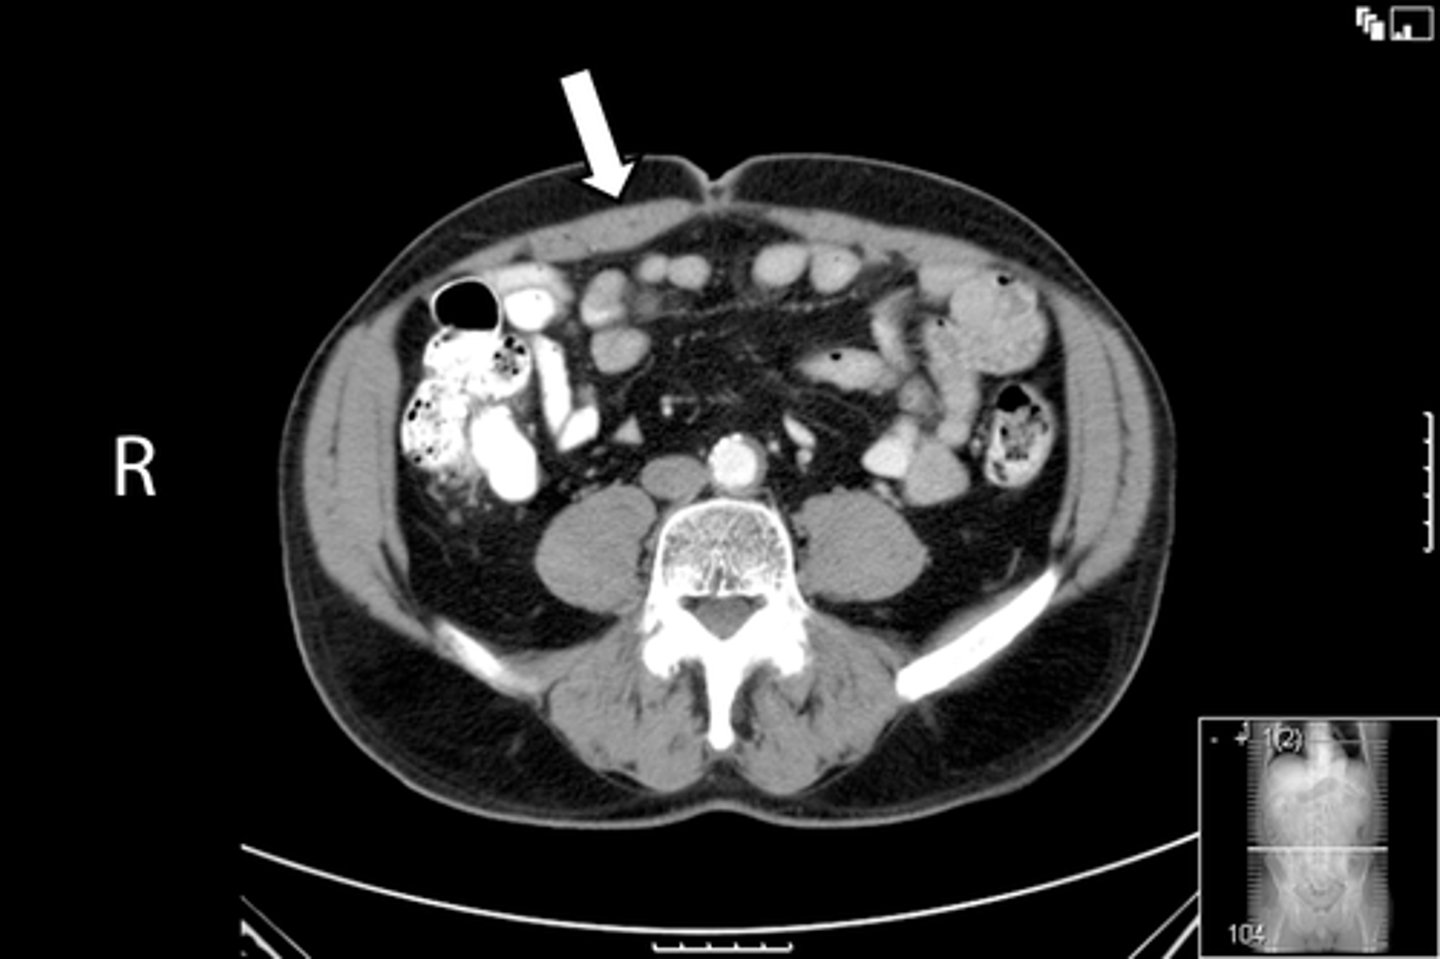

<p>What is indicated in the image?</p>

7

New cards

Ilium

What is indicated in the image?

8

Ischial spine